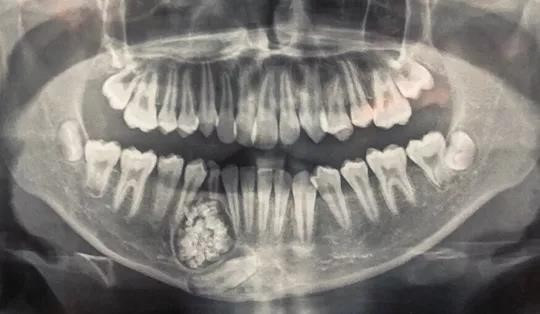

Ngày 15/6, bác sĩ Nguyễn Đức Tuấn, Trưởng khoa Răng Hàm Mặt, Bệnh viện Đa khoa tỉnh Khánh Hòa, thông tin các bác sĩ của đơn vị này phối hợp Bệnh viên Răng Hàm Mặt Trung ương TP.HCM phẫu thuật, lấy gần 100 cái răng trong khối u ở hàm dưới của bệnh nhân H.G. K. (13 tuổi, ngụ thành phố Nha Trang, tỉnh Khánh Hòa).

Những chiếc răng nhỏ có đầy đủ thân, tủy và chân răng.

U răng với gần 100 chiếc răng nhỏ. Ảnh: Bệnh viện Đa khoa Khánh Hòa cung cấp.

Qua chụp X-quang, các bác sĩ phát hiện một khối u răng ở xương hàm dưới.

Theo bác sĩ Tuấn, u răng (hay còn gọi Odontoma) là một trong những loại u lành tính. U răng rất khó phát hiện, chỉ qua phim chụp X-quang mới có thể nhìn thấy.